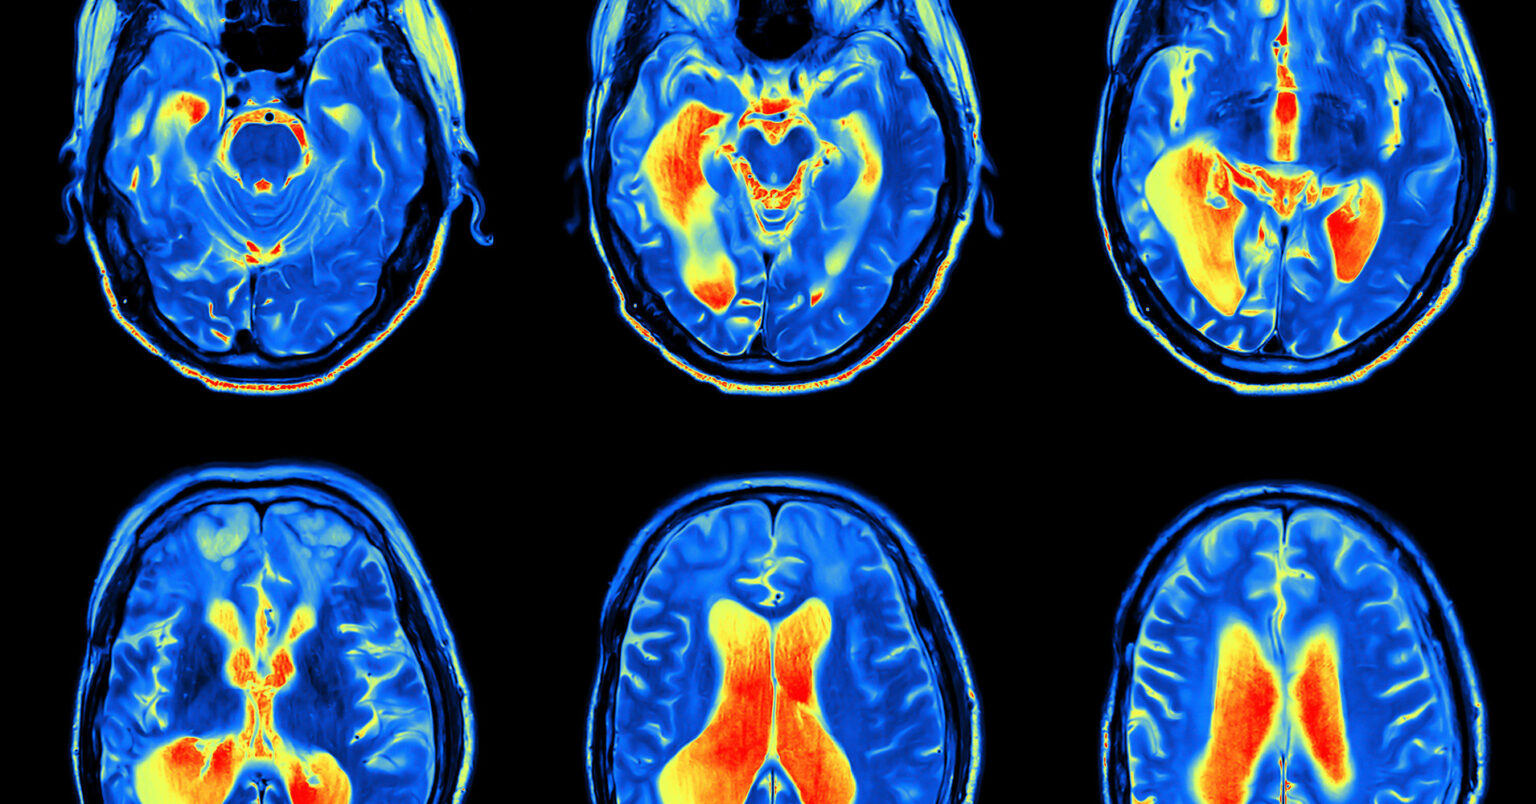

Human Brain, FMRI Scan - Stock Image - C038/8577 - Science Photo Library

www.sciencephoto.com

www.sciencephoto.com

fmri scan